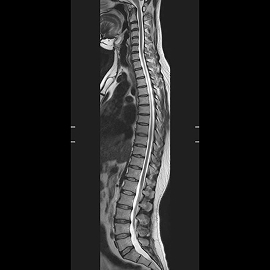

MRIの検査画像例

MRI

PHILIPS社製Ingenia 1.5TMRIを使用しています。開口径が従来の装置より広いワイドボアタイプとなり、より圧迫感の少ない、患者さんに優しい検査環境を実現できます。また、世界初のデジタルコイルを採用しており、ノイズが少なく診断能の高い画像が得られるようになりました。

新しい技術として、体動補正技術(MultiVane)や金属アーチファクト抑制技術(MARS)が使えるようになり、画質が格段に改善しております。

また、これまでの呼吸同期に加え、横隔膜の動きをリアルタイムに観察できるNavigator echo法が使えるようになり、肝臓領域やMRCP検査においてより高精細な同期撮影が可能となりました。

また、全脊椎検査やDWIBSなど以前の装置では多くの時間を費やしていた広範囲の検査に対して特にスループットが向上し、以前よりも短時間での検査が可能となりました。